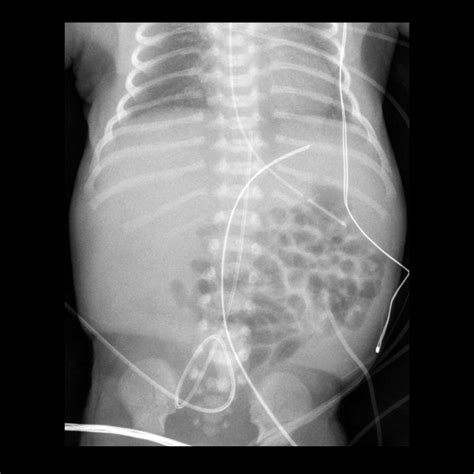

3. Insertion: The catheter is gently inserted into the umbilical vein, which is identified by its larger size and bluish color compared to the arteries. The catheter is advanced until it reaches the desired position, typically confirmed by ultrasound or X-ray.

5. Verification: The position of the catheter is verified using imaging techniques to ensure it is correctly placed in the inferior vena cava.

• Malposition: Incorrect placement of the catheter can lead to ineffective therapy or complications such as arrhythmias.

• umbilical venous catheter x ray